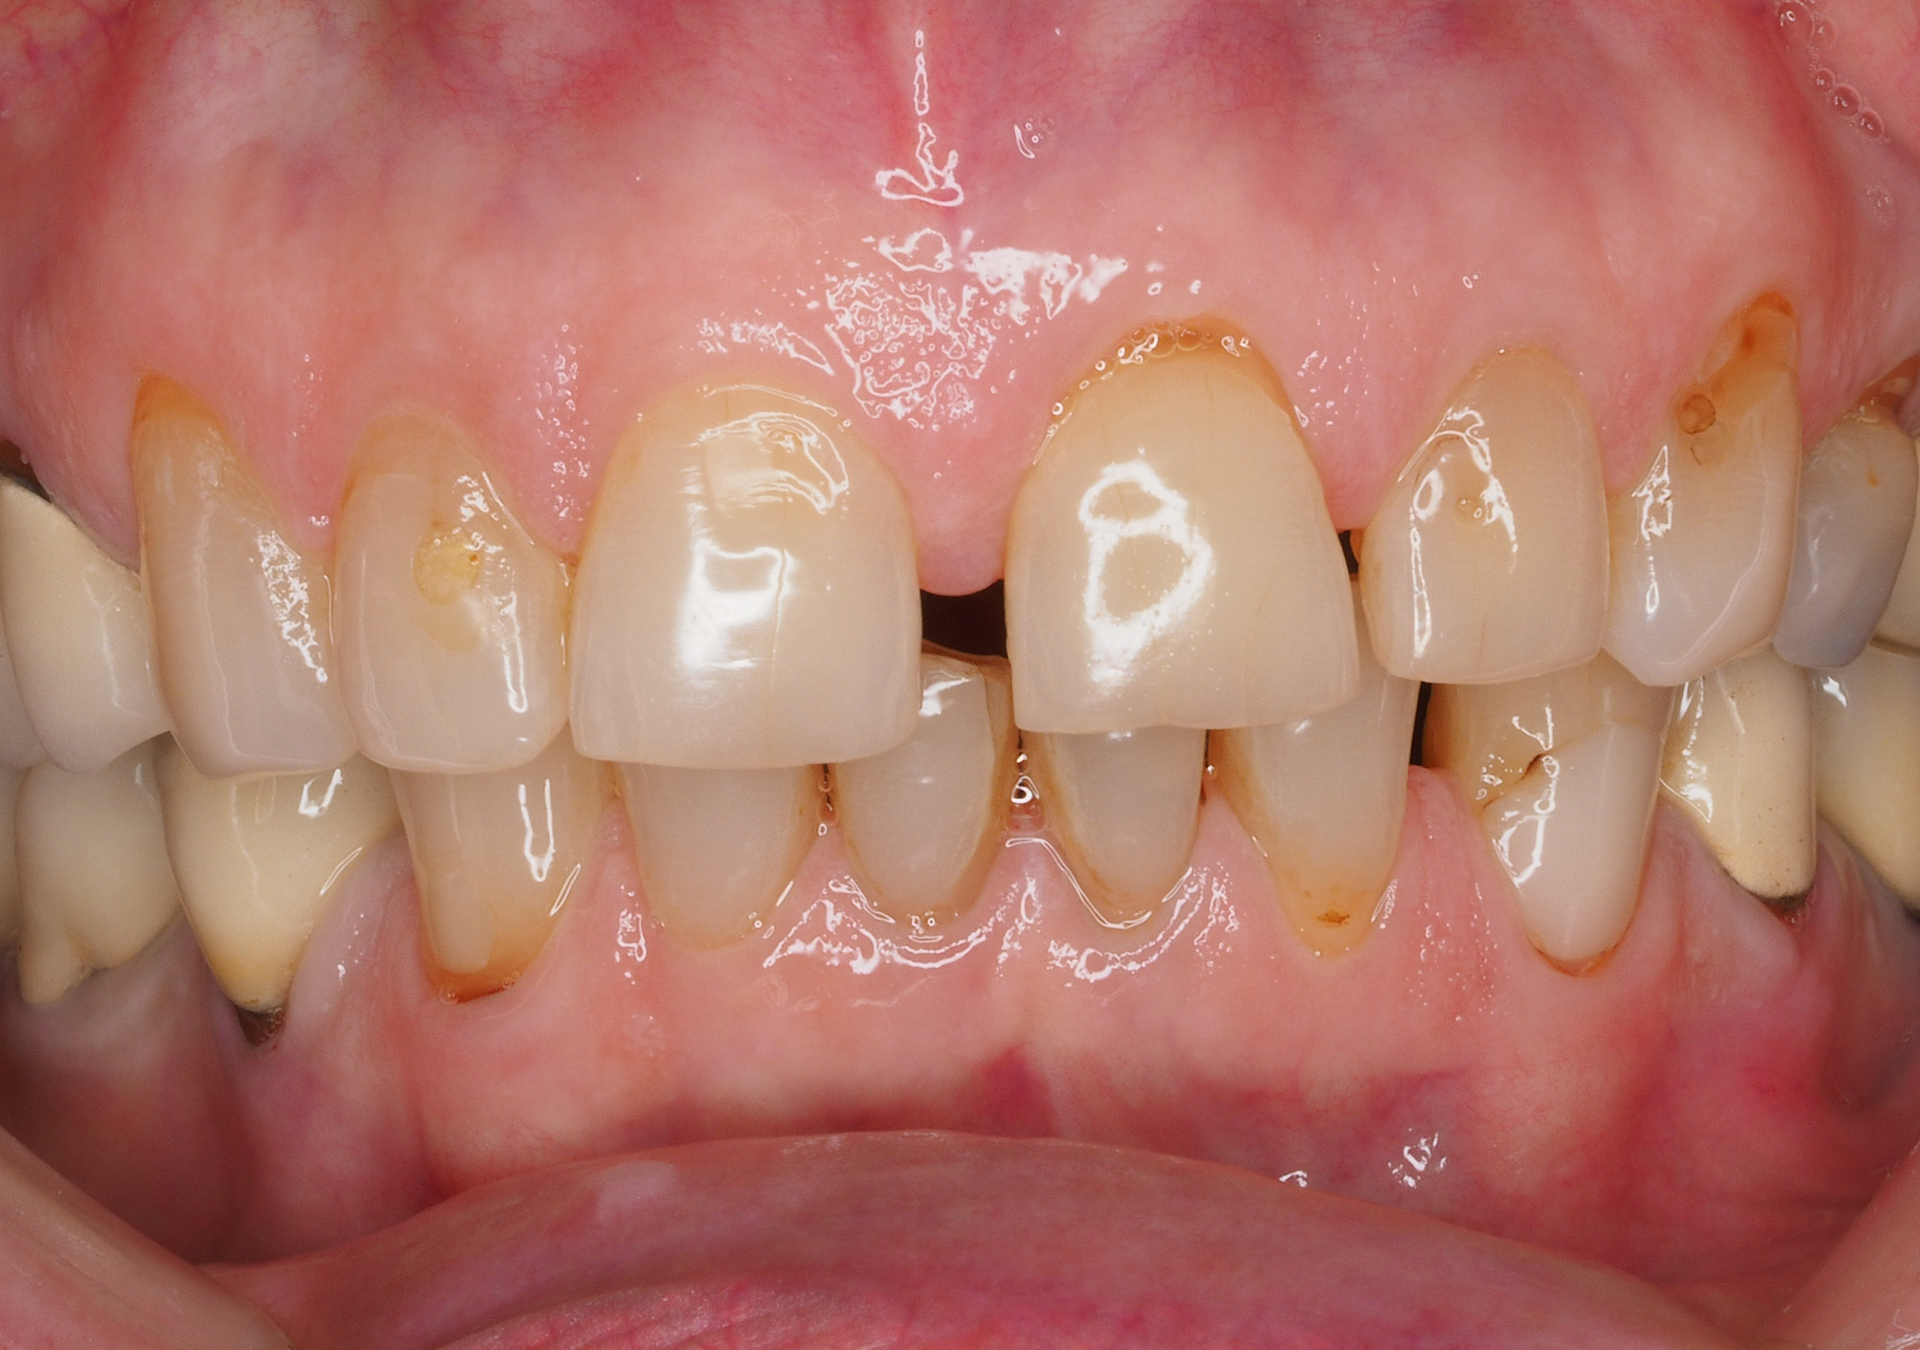

Restauración

con composite (Resinas)

- 25 años de experiencia en restauraciones de resina composite tanto en sectores anteriores como posteriores.

- Técnicas de aislamiento para garantizar la longevidad y la integridad de la restauración.

- Resultados estéticos comparables a la cerámica, de larga durabilidad.